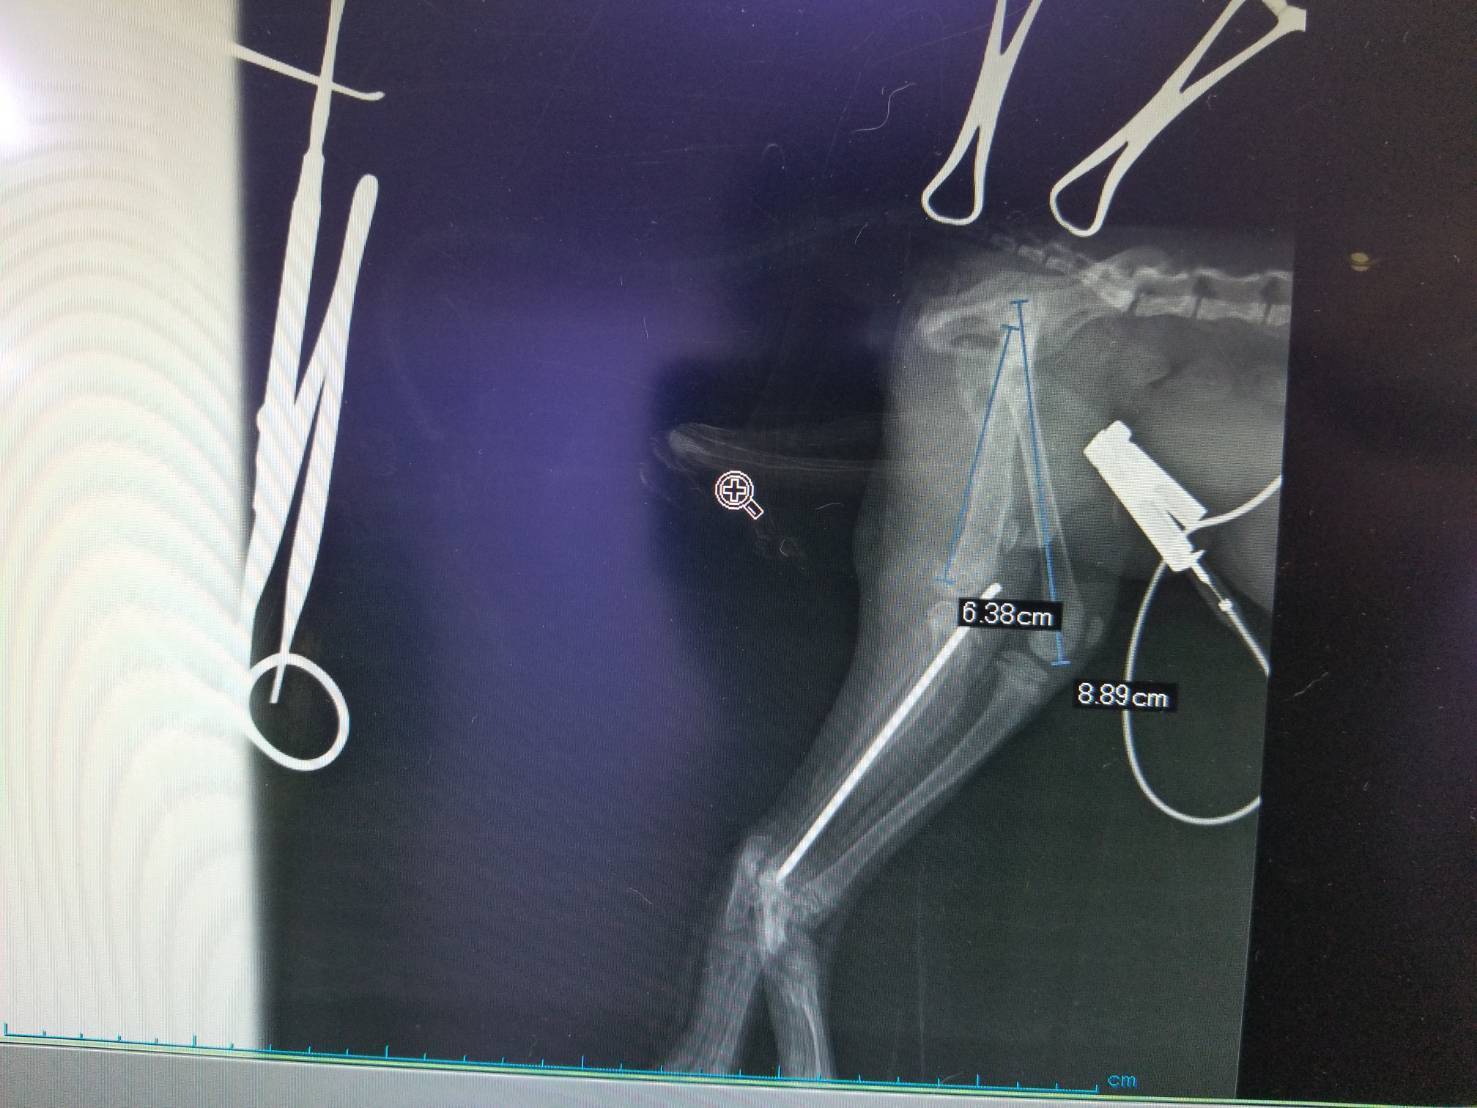

本日、ハコちゃんの二回目の手術を行いました。

内容としてはピン・プレートの除去手術と本来存在しないはずの骨の除去です。

結果としては成功に終わりました!また、獣医師さんの判断で一本ピンを残した状態にしてありますが、こちらも様子を見て必要なら避妊手術を行う際に合わせて抜く予定です。

また、手術としては成功の裏に終わり骨折もきれいに治りましたが、肝心の骨折した足の関節間にある潤滑液が少なくなっているためもしかしたら上手く使えなくなってしまう可能性があるとのご指摘を獣医師さんよりいただきました。